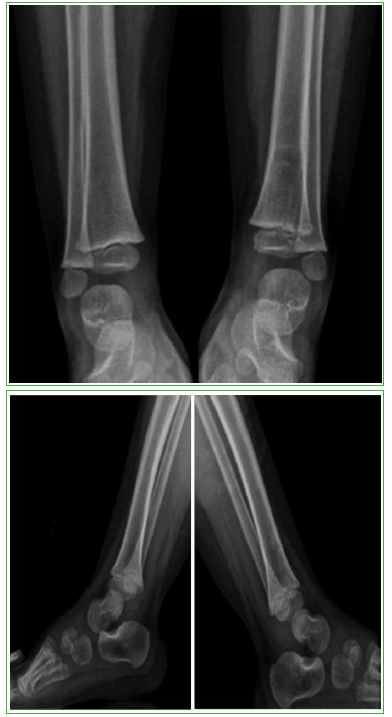

Osteomielitis de tibia secundaria a la vacuna BCG en un paciente pediátrico inmunocompetente. Reporte de un caso